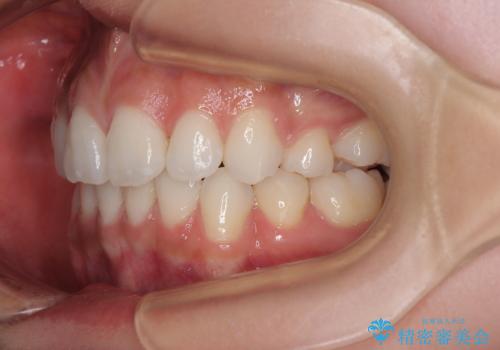

右下の埋伏歯はやはり癒着しており、抜歯の後にインプラントを埋入することとなりました。

埋伏歯の牽引や、奥歯の咬み合わせ改善、インプラント補綴治療と治療期間が延びてしまう要素が多く、治療は難航しましたが、最終的に非常に満足のいく仕上がりとなりました。